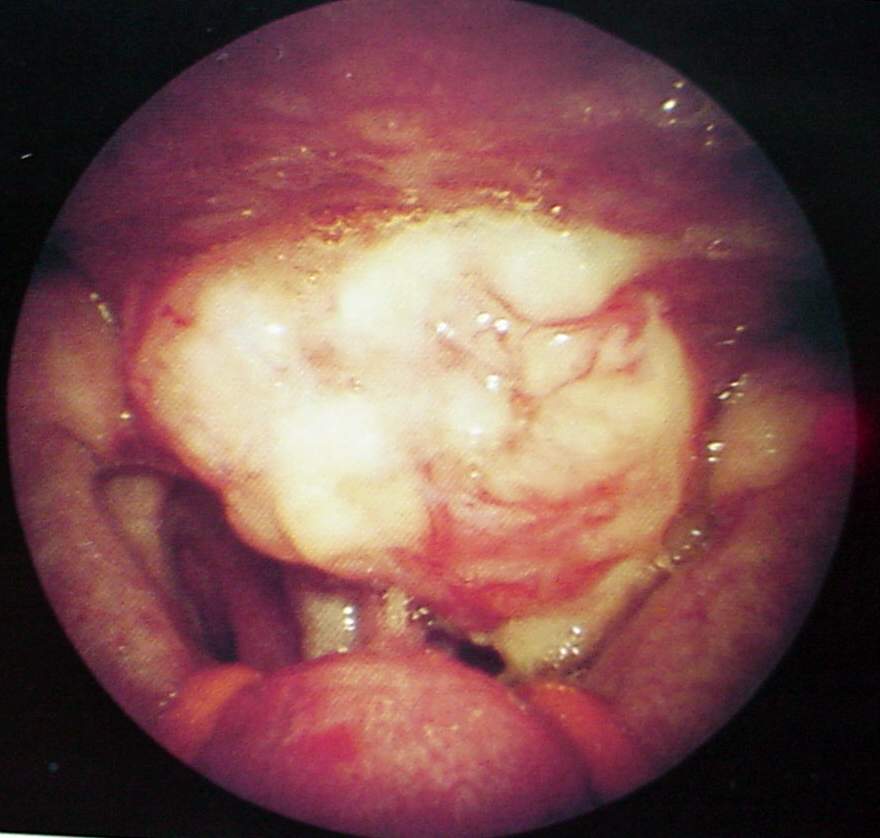

Pharynx and Esophagus Clinical Photos for Static Stations